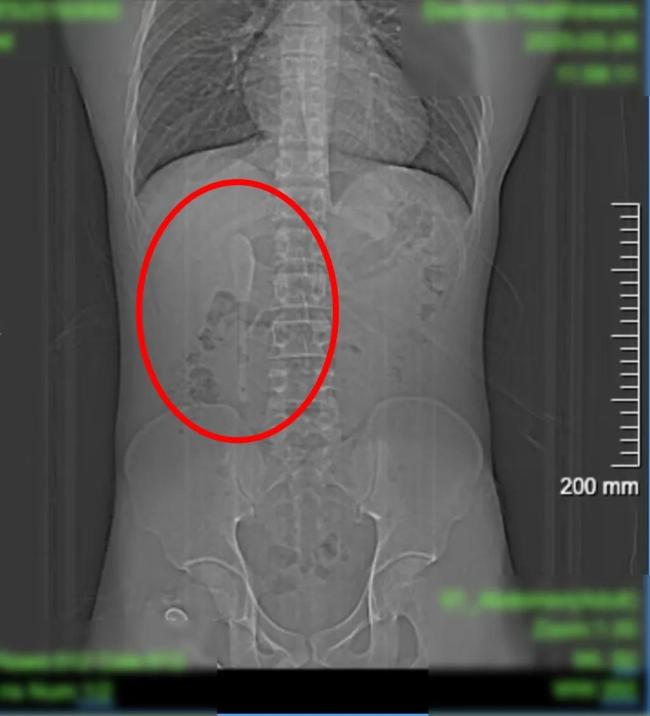

一个15厘米长的咖啡勺被29岁的男子小言“遗忘”在腹中长达半年,原因是他以为那是在做梦。近期,小言因外卖吃出塑料异物前往复旦大学附属中山医院急诊检查,却意外发现腹中躺着一支近15厘米长的咖啡勺。CT显示这支勺状物体横亘于十二指肠球部与降部交界的生理狭窄处,稍有不慎即可能刺穿肠壁,引发腹膜炎或大出血。

这支被遗忘的勺子历经6个月胃肠蠕动,最终精准卡进十二指肠球部与降部交界处。此处腔隙狭窄且肠壁极为菲薄,异物极易嵌顿,稍有不慎容易造成穿孔。中山医院内镜中心主任周平红教授解释:“勺子陶瓷质地光滑细长,十二指肠球降交界又是人体上消化道的生理狭窄处,内镜下取出难度极大。若失败,只能开腹手术。”